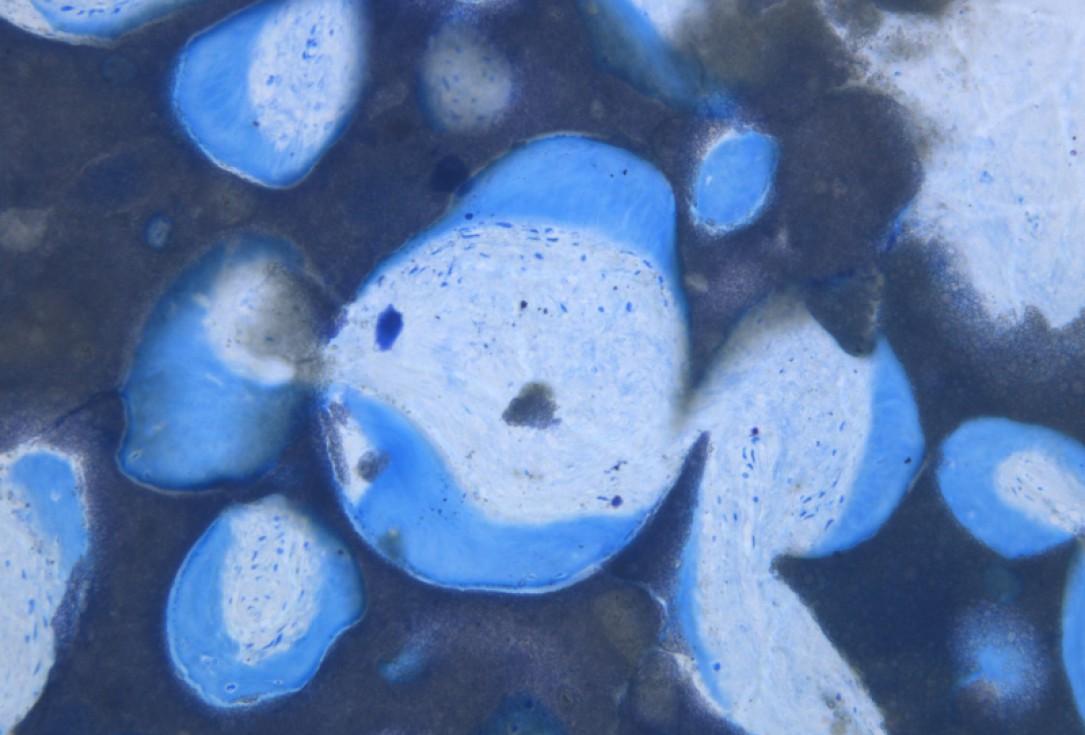

16/20 - re-entry: maxresorb® particles integrated into newly formed boneGBR with maxresorb® & Jason® membrane - Prof. Dr. Dr. D. Rothamel

18/20 - Histology showing the integration of maxresorb®GBR with maxresorb® & Jason® membrane - Prof. Dr. Dr. D. Rothamel